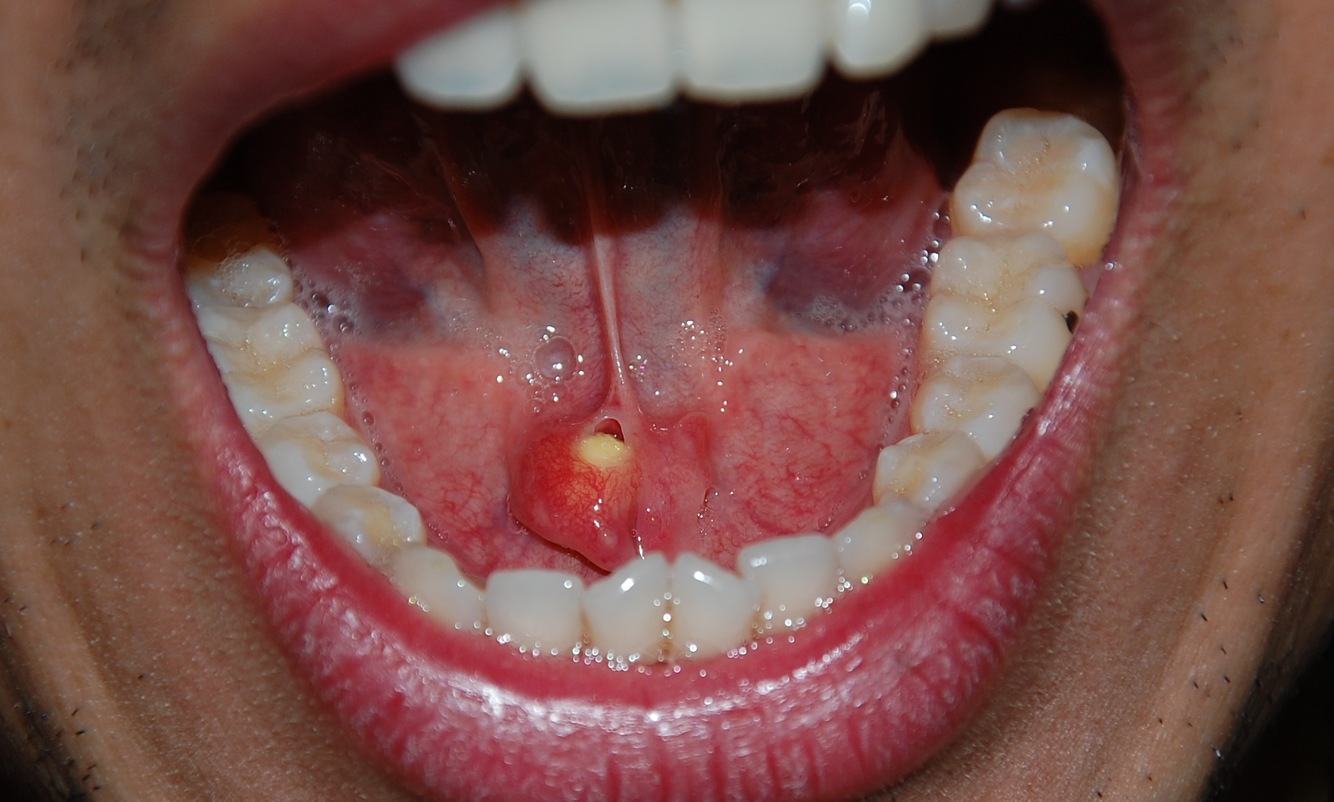

Mucus Extravasation Phenomenon

Spillage of mucin into the soft tissue due to rupture of a salivary gland duct, usually caused by trauma.

May fill with fibrotic tissue and develop into a fibroma

More superficial –> clear

may rupture and pts may think they are recurring “blisters”

More deep –> Mucosal colored, purple due to blood

Most common locations for mucocele

Lower lip (81%)

FOM

Anterior ventral tongue

Buccal Mucosa

Ranula

Mucoceles in the floor of the mouth – usually lateral to the midline

Sublingual gland duct